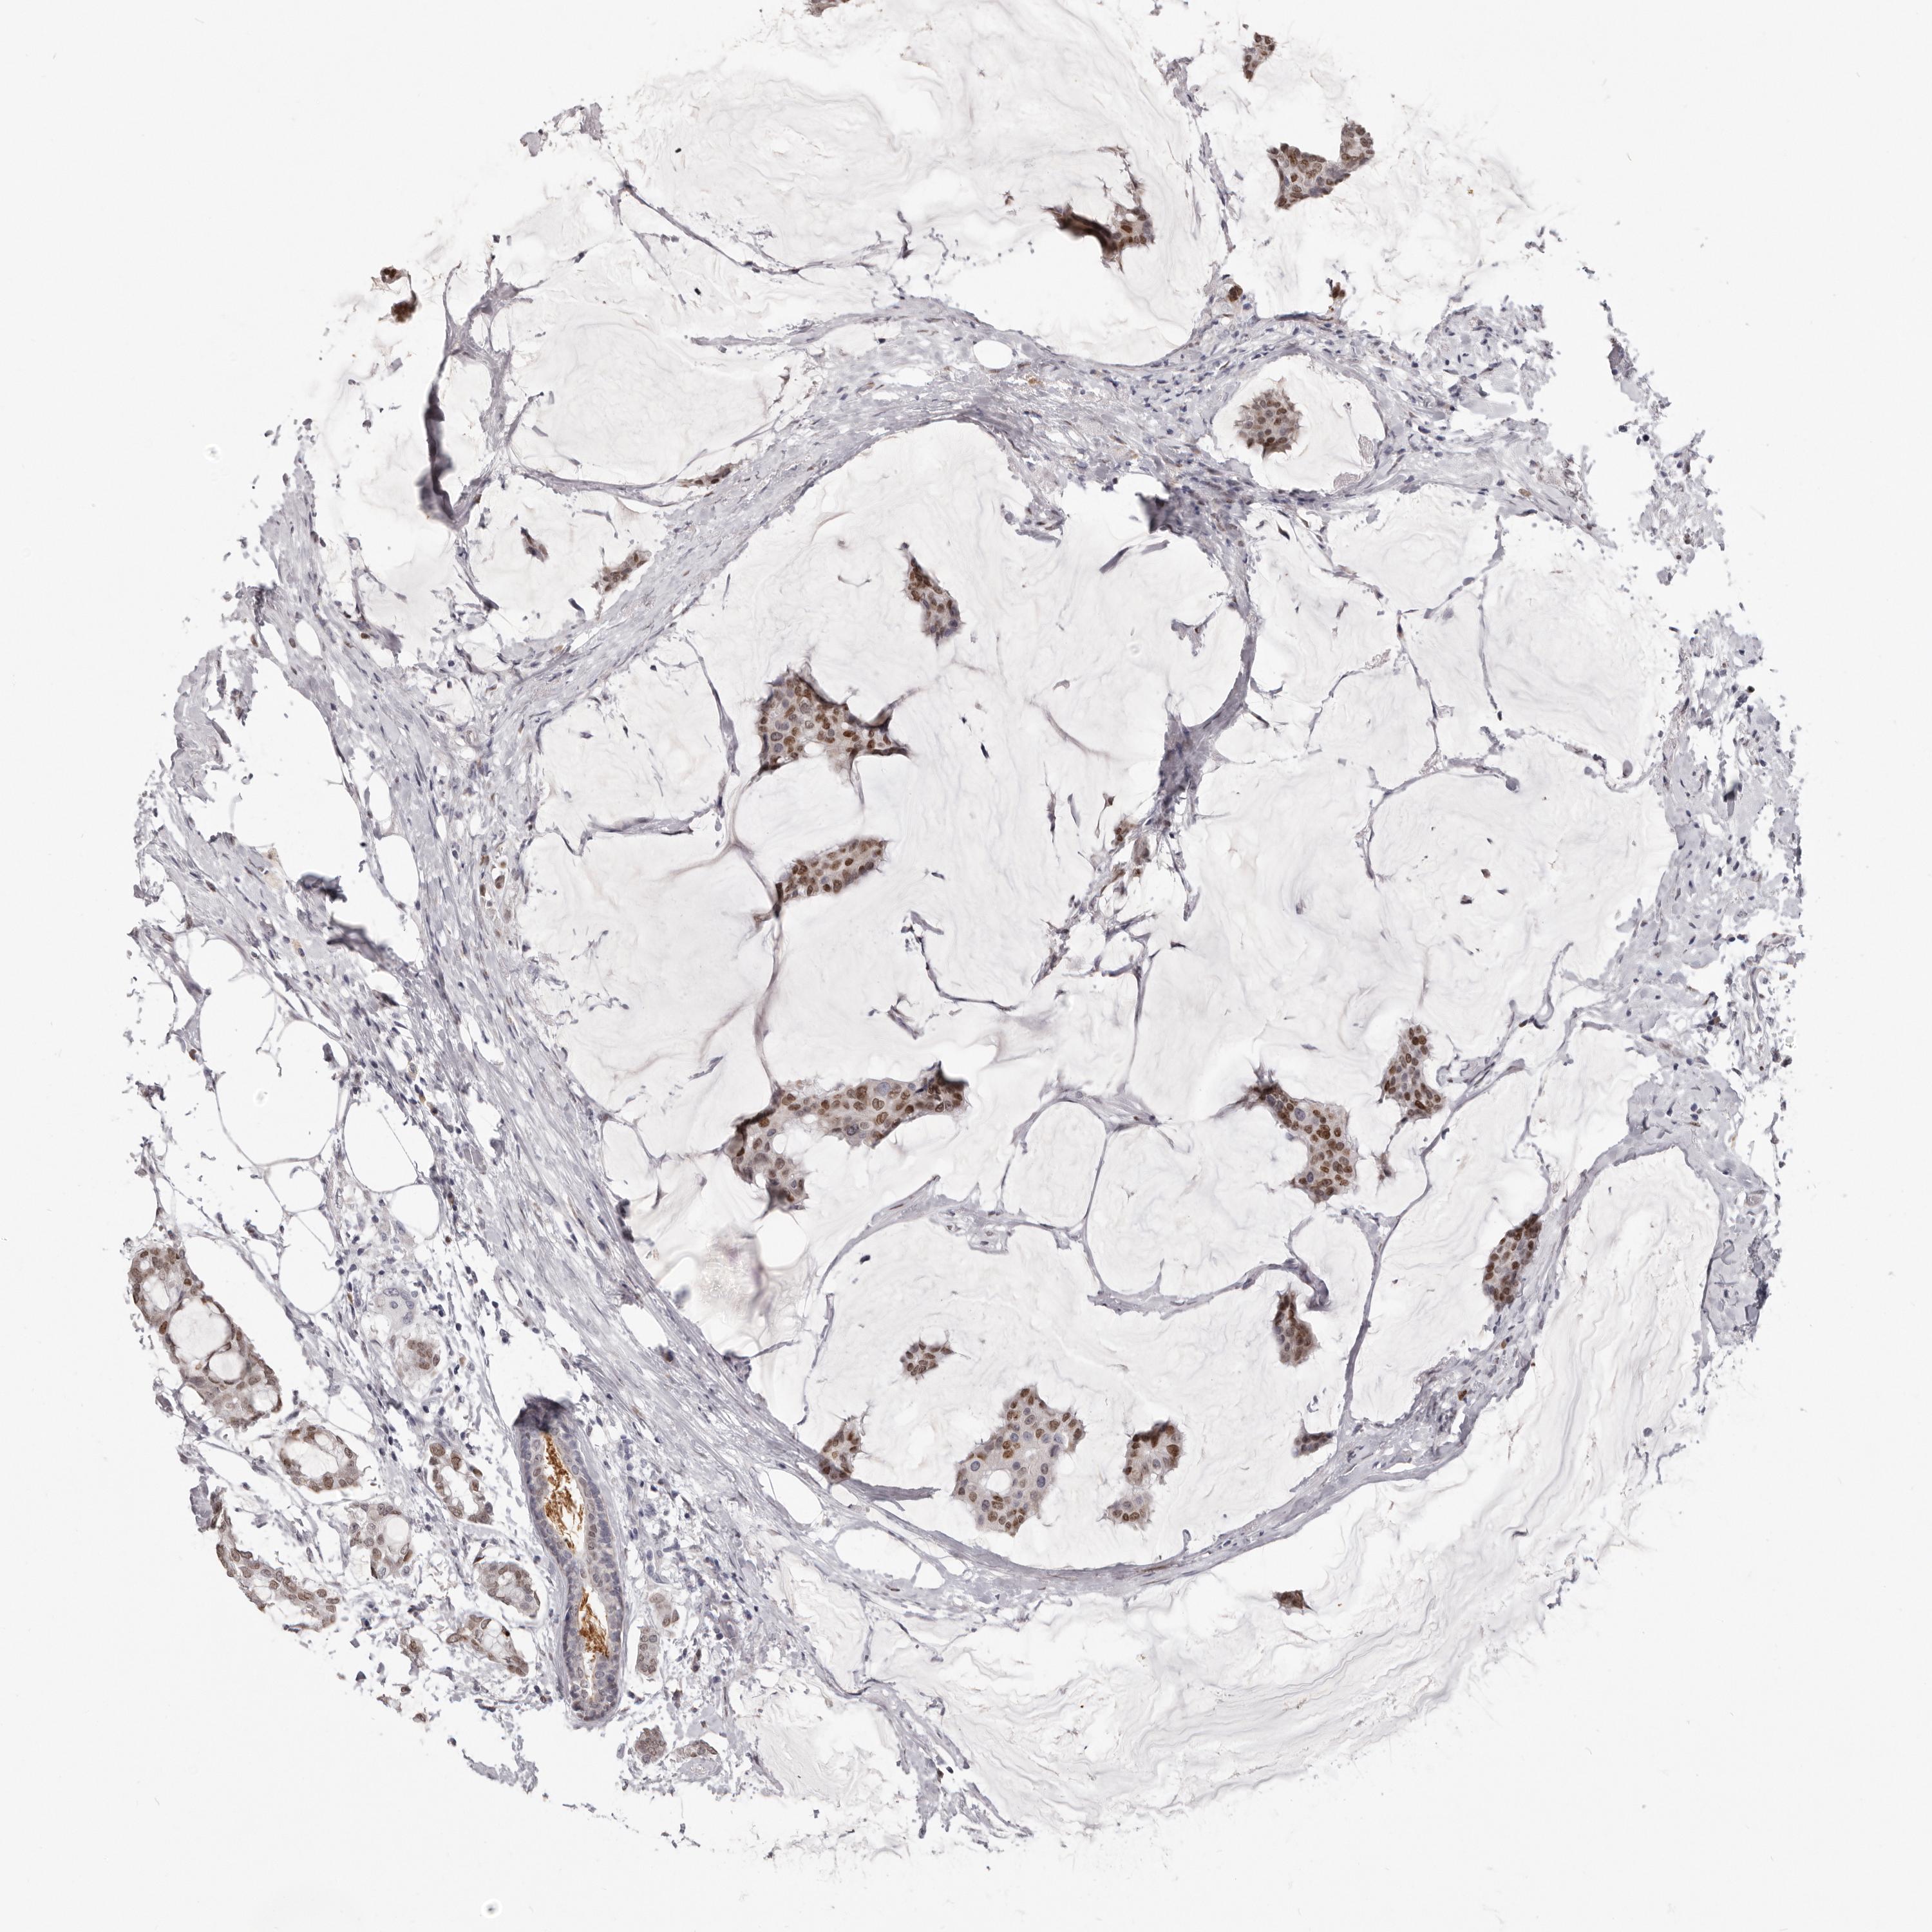

CANCER BREAST CANCER Show tissue menu

BRCA TCGA BRCA VALIDATION PROTEIN EXPRESSION

Breast cancer

Human cancer

Breast invasive carcinoma